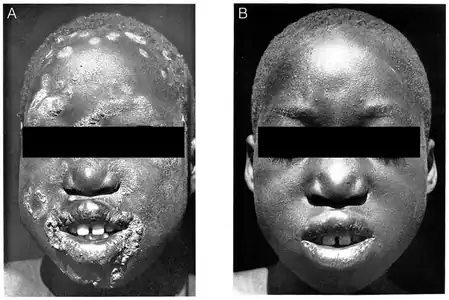

Within 8–10 hours of penicillin treatment, bacteria can no longer be found in lesion biopsies.[2] Primary and secondary lesions usually heal in 2–4 weeks; bone pain may improve within two days.[13] If treated early enough, bone deformities may reverse and heal.[2] Primary and secondary stage lesions may heal completely, but the destructive changes of tertiary yaws are largely irreversible.

Secondary yaws in the left armpit of a ten-year-old, 2020

Secondary yaws in the left armpit of a ten-year-old, 2020 Same person, 2 weeks and 3.5 months after a single-dose azithromycin

Same person, 2 weeks and 3.5 months after a single-dose azithromycin Before and two weeks after a single injection of benzathine penicillin, 1950s.

Before and two weeks after a single injection of benzathine penicillin, 1950s.